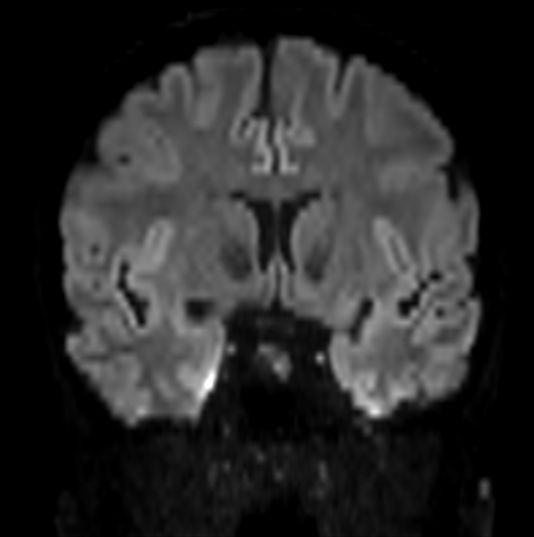

Axial DWI b1000 (Coronal reformat)